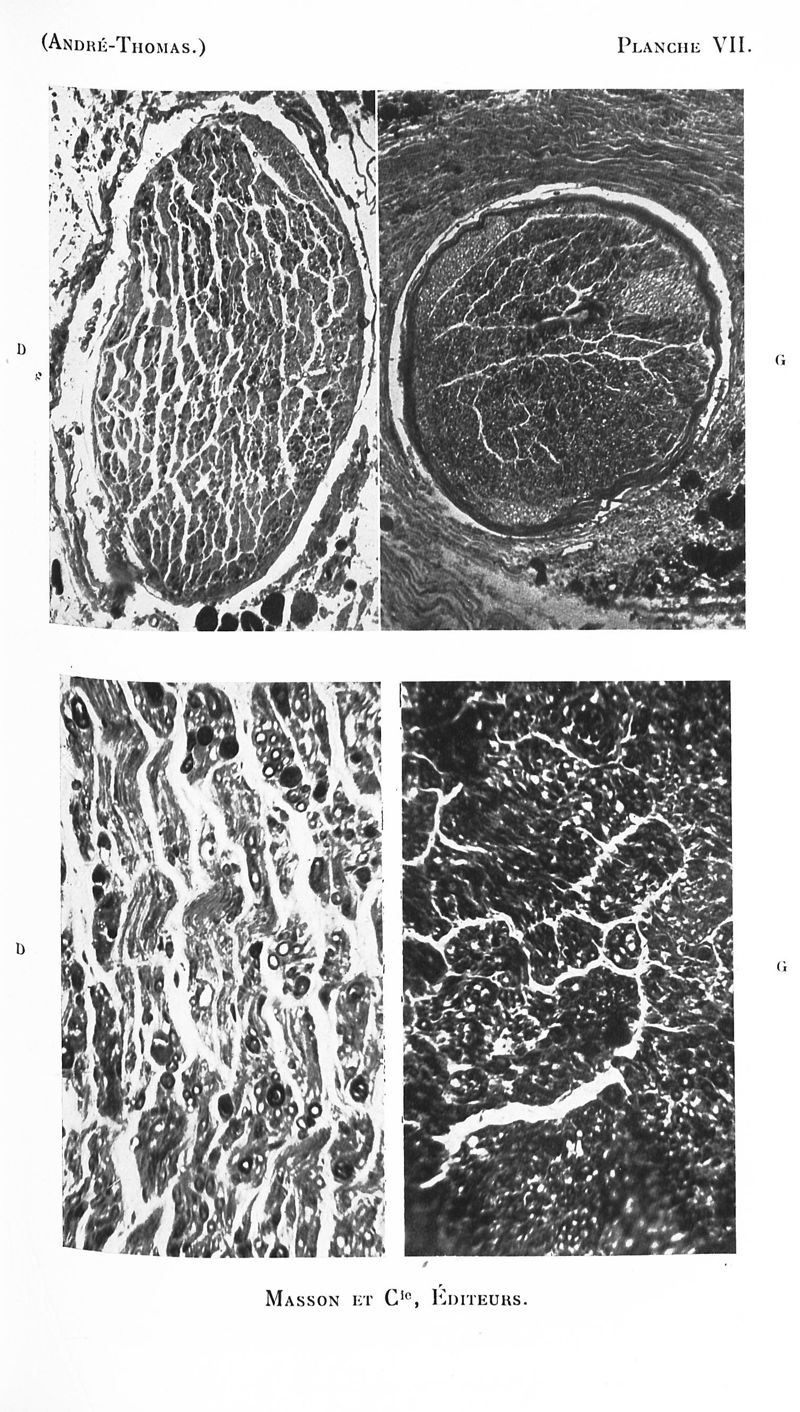

Revue neurologique

1926, vol 1. - Paris : Masson , 1926.